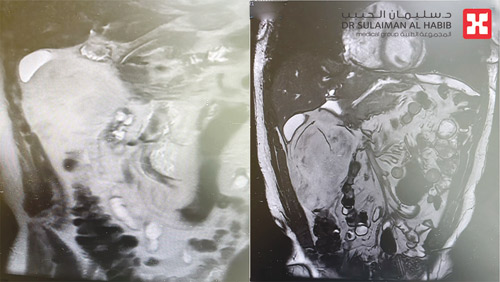

وقال د. الرواشدة أن الفريق الطبي أخضع المريض لفحوصات طبية دقيقة حيث بينت النتائج وجود ورم ضخم حجمه «15 × 10 × 9» سم، منشأه الغشاء البريتوني الخلفي للبطن، ومتشعب وضاغط بشكل حاد على الاثني عشر والكلية اليمنى والقولون، وخلص الفريق الطبي إلى خطة علاجية ارتكزت على التدخل الجراحي، حيث أجريت للمريض عملية جراحية تم فيها استئصال كتلة الورم من البطن بدقة عالية، مع الحفاظ على سلامة الأعضاء التي التصق بها، واستمرت العملية لمدة ساعتين، وتوجت جهود الفريق الطبي ولله الحمد بالنجاح التام. وقد خرج المريض إلى منزله وهو بحالة صحية ممتازة وقد تخلص من كافة الأعراض التي كان يشكو منها. وقد أظهرت الفحوصات الطبية اللاحقة للعملية أنه تم إزالة الورم بالكامل.